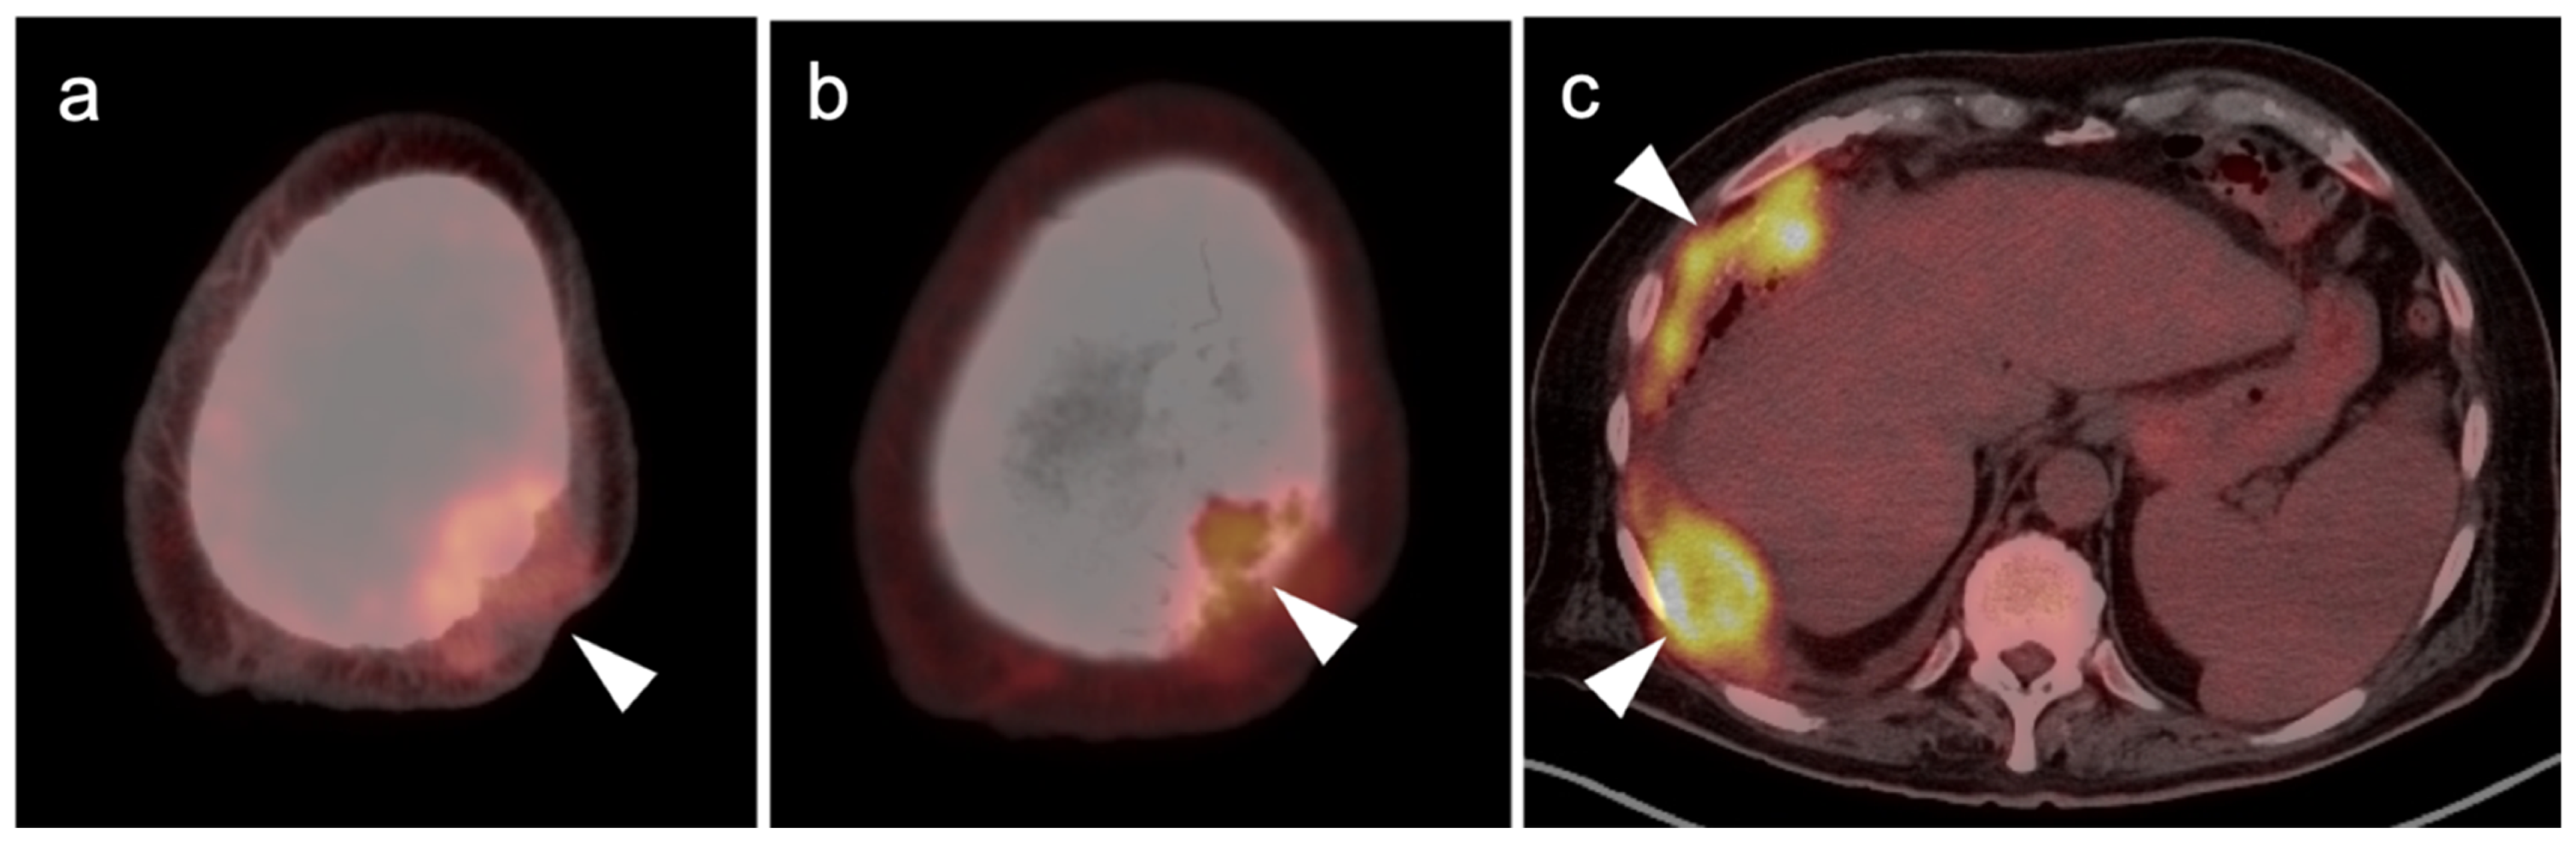

3.2.1. Chondrosarcoma

3.2.2. Osteosarcoma

- Subhawong, T.K.; Winn, A.; Shemesh, S.; Pretell-Mazzini, J. F-18 FDG PET differentiation of benign from malignant chondroid neoplasms: A systematic review of the literature. Skelet. Radiol. 2017, 46, 1233–1239. [Google Scholar] [CrossRef]

- Brenner, W.; Conrad, E.U.; Eary, J.F. FDG PET imaging for grading and prediction of outcome in chondrosarcoma patients. Eur. J. Pediatr. 2004, 31, 189–195. [Google Scholar] [CrossRef]

- Mirabello, L.; Troisi, R.J.; Savage, S.A. Osteosarcoma incidence and survival rates from 1973 to 2004: Data from the Surveillance, Epidemiology, and End Results Program. Cancer 2009, 115, 1531–1543. [Google Scholar] [CrossRef] [Green Version]

- Aryal, A.; Kumar, V.S.; Shamim, S.A.; Gamanagatti, S.; Alam Khan, S. What Is the Comparative Ability of 18F-FDG PET/CT, 99mTc-MDP Skeletal Scintigraphy, and Whole-body MRI as a Staging Investigation to Detect Skeletal Metastases in Patients with Osteosarcoma and Ewing Sarcoma? Clin. Orthop. Relat. Res. 2021, 479, 1768–1779. [Google Scholar] [CrossRef]